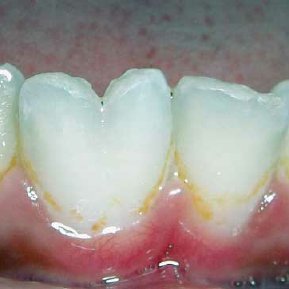

dens Evaginatus :

talon cusp, has pulp, dentin , enamel ( dont extract)